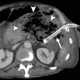

Sepsis

Sepsis is a life-threatening condition that arises when the body's response to infection causes injury to its own tissues and organs. This initial stage is followed by suppression of the immune system. [Source: Wikipedia ]